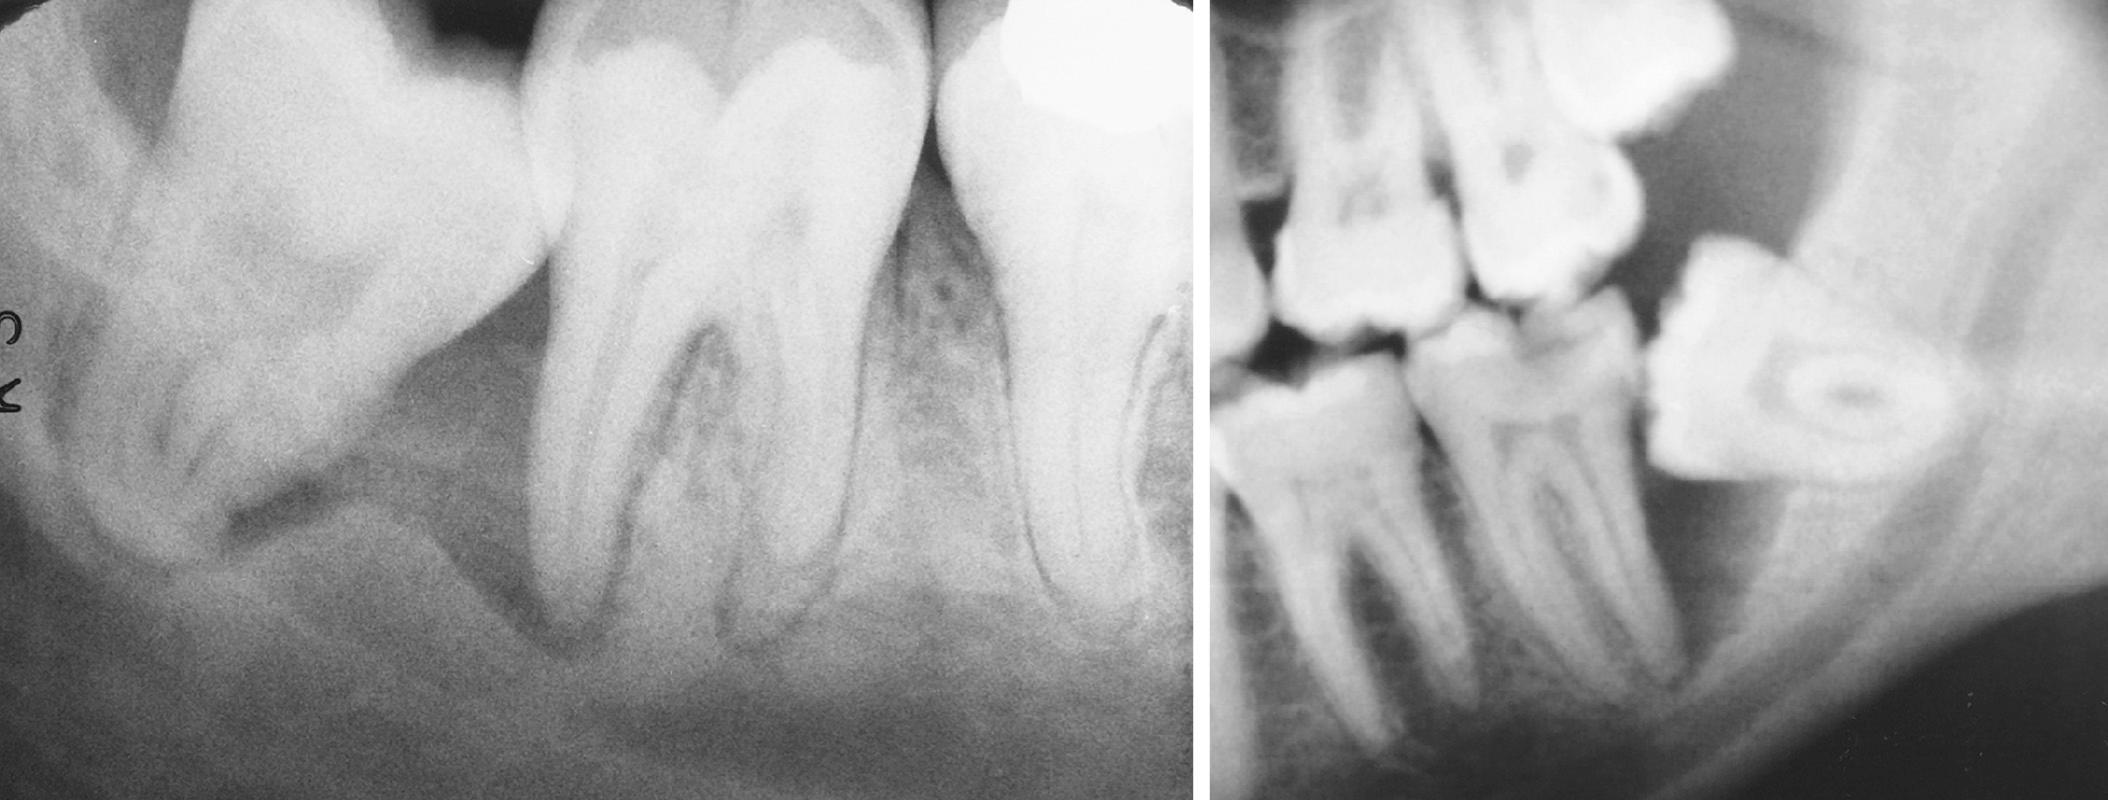

Occasionally an impacted tooth causes sufficient pressure on the root of an adjacent tooth to cause external root resorption ( Fig. 10.7 ). Although the process by which root resorption occurs is not well understood, it appears to be similar to the resorption process primary teeth undergo during the eruptive process of the succedaneous teeth. Removal of the impacted tooth may result in salvage of the adjacent tooth by cemental repair. Endodontic therapy may be required to save these teeth.

Fig. 10.7, (A) Root resorption of a second molar as result of an impacted third molar. (B) Root resorption of maxillary lateral incisors as a result of an impacted canine.